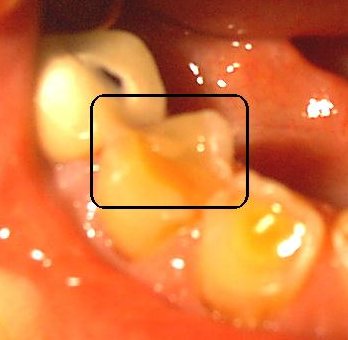

10:30 a.m. While I was eating some nuts, I kept thinking that there was some stuck in one of the crevasses of a bottom tooth on the right. When I looked in the mirror, there literally is a new mound of enamel formation right on top of or in what was the crevasse of the tooth that was worn down to the dentine.

The enamel lump is in the center back of the tooth.

12-29-2000

When I put my teeth together, I can feel the lump of enamel, It has the appearance that there is a rounded point of a new tooth building up through the old one. This does help enhance chewing for the tooth was badly worn in that area, but I can feel it when I chew. The tooth does feel a little funny right now. There is a cavity on the outside of this tooth close to the gum line, but I wonder why it isn't repairing the cavity first instead of rebuilding the top, maybe that is next?